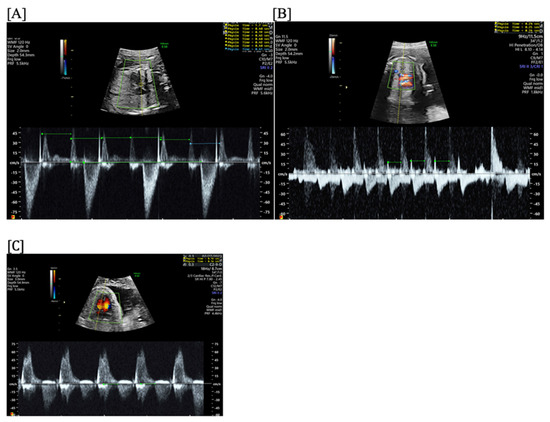

- Short VA SVT (Figure 3 and Figure 4) demonstrates a ventricular–atrial (VA) interval that is less than half of the ventricular–ventricular (VV) interval (VA:AV ratio < 1) and a sudden onset and termination of tachycardia; tachycardia usually terminates with a non-conducted atrial contraction. Short VA SVT includes AVRT (also known as orthodromic reciprocating tachycardia, ORT) and atrioventricular nodal reentrant tachycardia (AVNRT). Short VA SVT typically presents after 18 weeks of gestation.